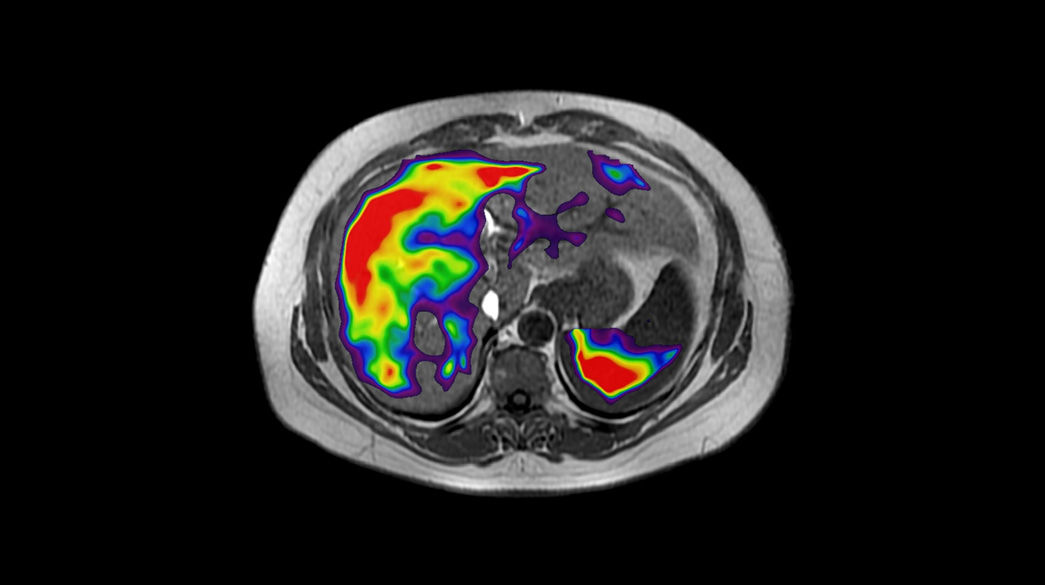

Body MRI for SIGNA™

Fast body MR imaging techniques to capture breast, abdominal and pelvic anatomy on any patient, with great flexibility.

Body MRI imaging applications

Precision and personalization